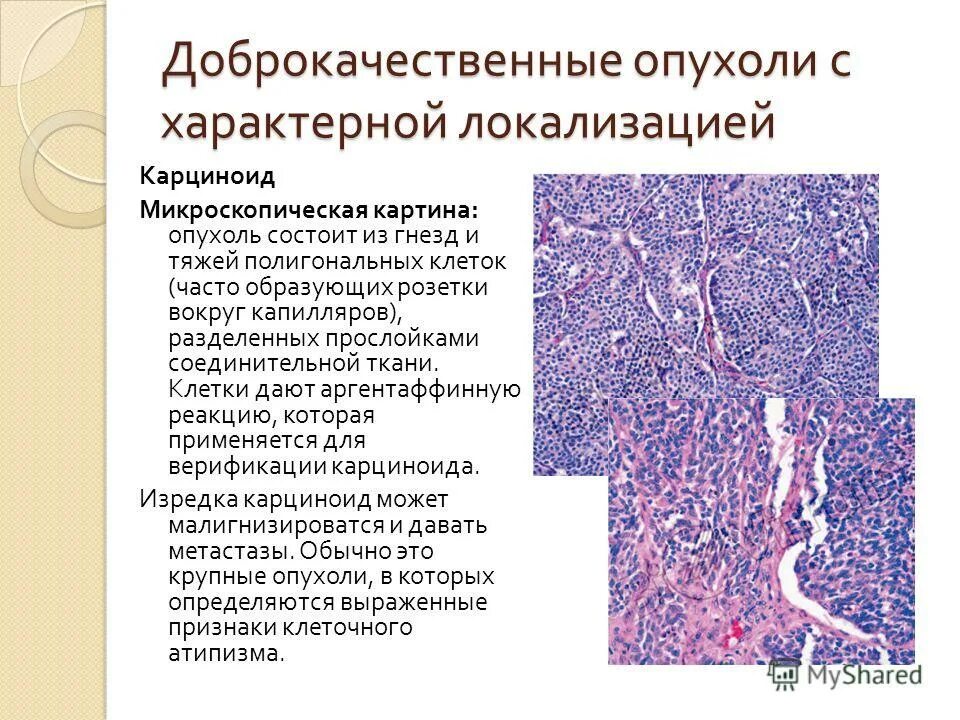

Доброкачественная злокачественная опухоль головного мозга мрт. Глиома головного мозга мрт. Опухоль головного мозга на кт. Карциноид червеобразного отростка гистология. Карциноид кишечника гистология. Карциноид червеобразного отростка патанатомия. Карциноидная опухоль микропрепарат.

Карциноид червеобразного отростка гистология. Карциноид кишечника гистология. Карциноид червеобразного отростка патанатомия. Карциноидная опухоль микропрепарат. Мрт головного мозга с контрастированием. Мрт с контрастированием опухоль. Мрт головы с контрастом. Магнитно резонансная томография с контрастом головного мозга.